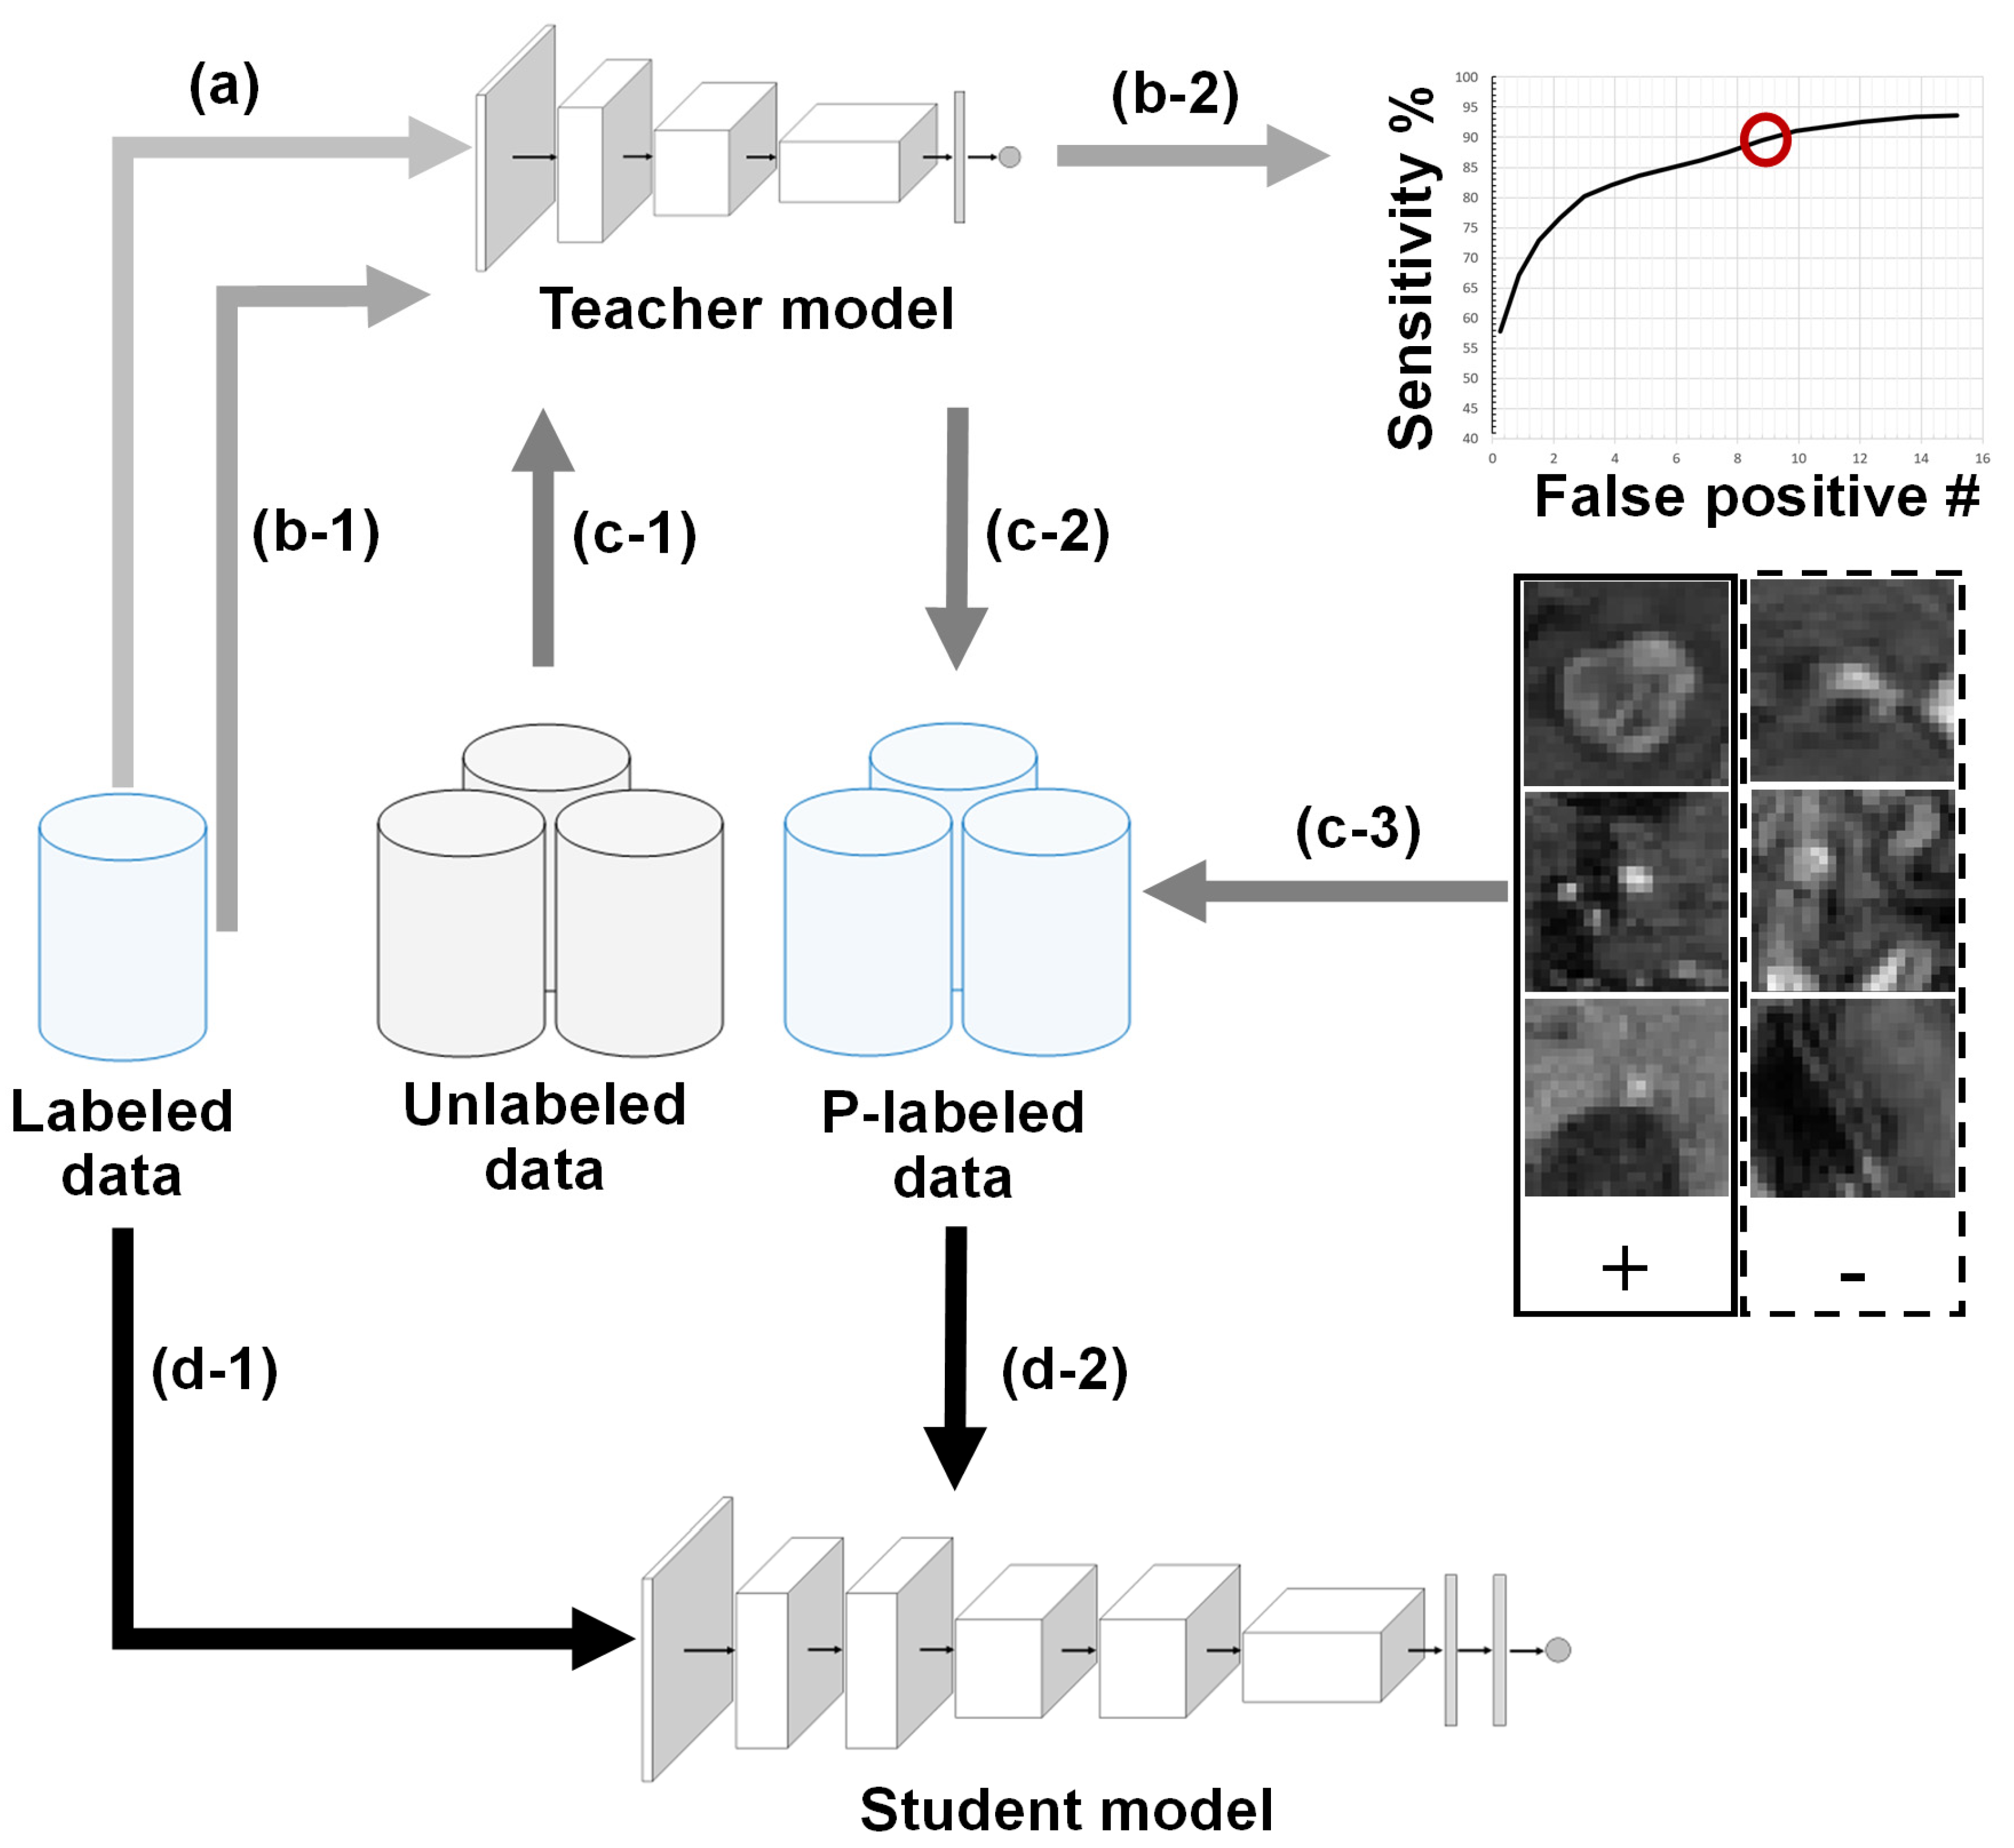

2.1. BM Detection Framework Overview

2.2. Teacher–Student Models and Noising Mechanisms

2.3. Technical Contribution: Sensitivity-Based NS Algorithm